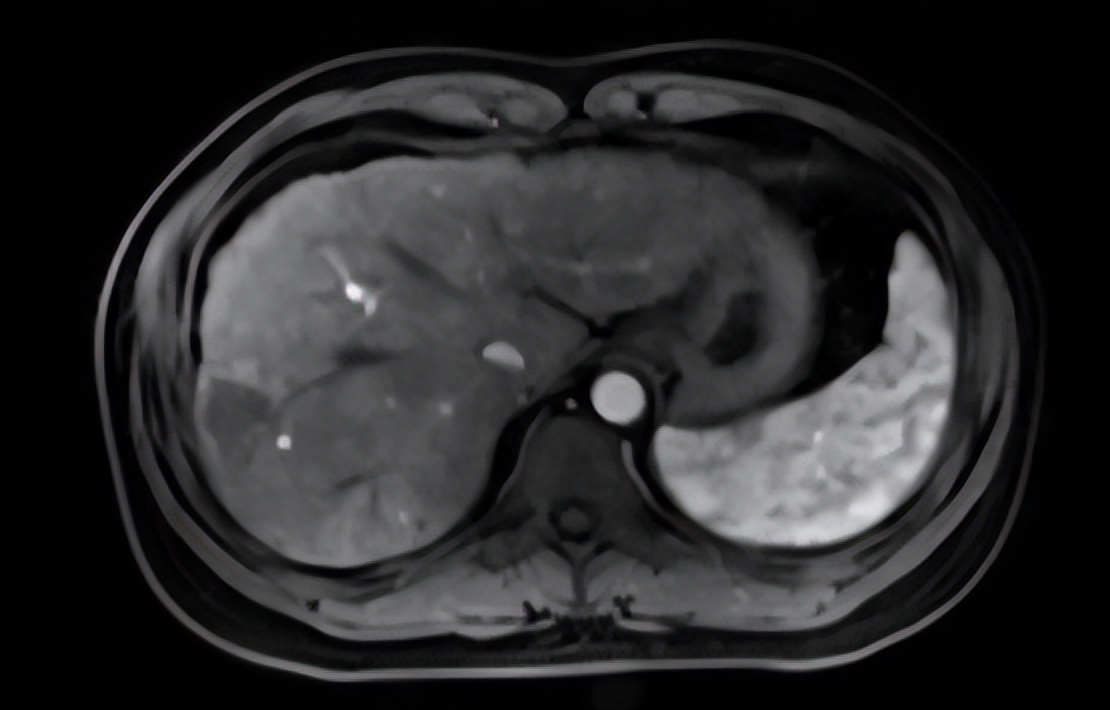

术后增强磁共振提示肿瘤组织无增强